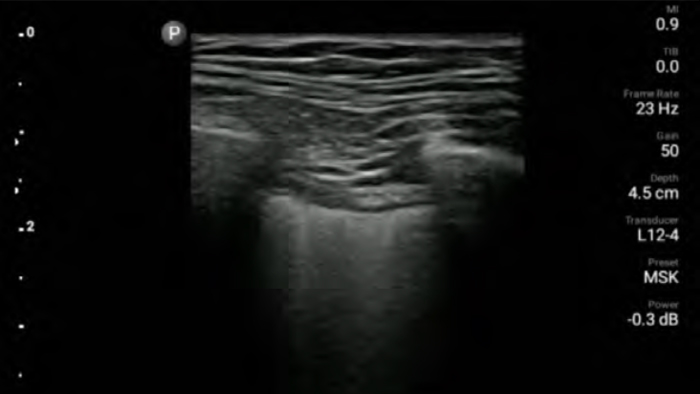

Reduce complications in needle guided procedures

Lumify handheld ultrasound for anesthesiology helps you clearly visualize border definition with your needle placement, surrounding nerves, vessels and fascial planes.

Lumify L12-4 broadband linear array transducer